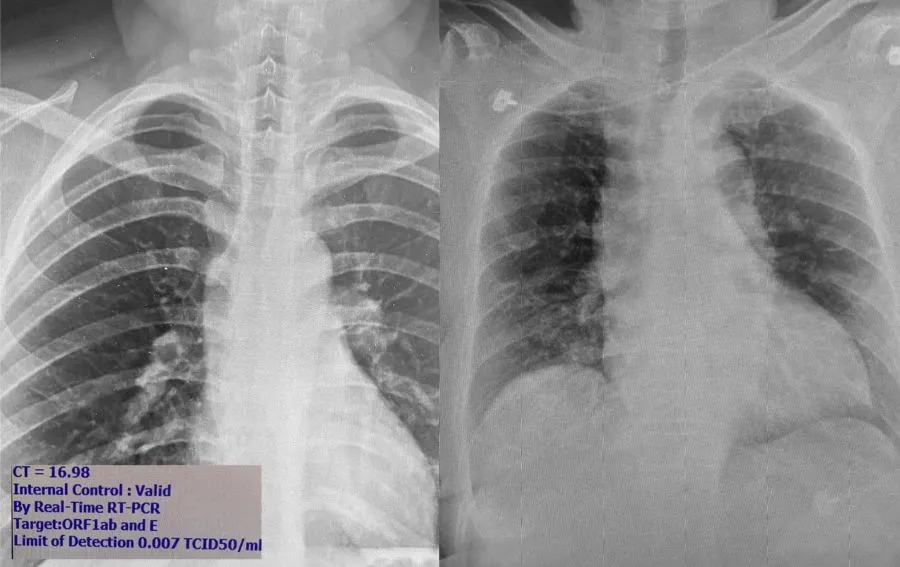

"นพ.โอภาส" เผย ฟิล์มเอกซเรย์ปอด ผู้ป่วยโควิด พบปอดอักเสบหนักติดเชื้อโควิด แต่ไม่มีอาการ

1. เชื้อแบ่งตัวได้ดีในจมูกและทางเดินหายใจ คนไม่มีอาการจะมีเชื้อในจมูกเยอะมากพร้อมที่จะแพร่กระจายเป็นวงกว้างเวลาไอ จามหรือพูด ในรูปภาพซ้าย ภาพถ่ายปอดผู้ที่ติดเชื้อที่ไม่มีอาการเลย เดินไปเดินมา ใช้ชีวิตเหมือนคนปกติ แต่เชื้อในจมูกค่า CT (cycle threshold) จากเครื่อง PCR บอกว่ามีปริมาณเชื้อในจมูกสูง มากเมื่อเทียบกับคนไข้ที่เคยเห็นในระลอกแรก ดังนั้นถ้าไม่ได้มาตรวจก็แพร่กระจายเชื้อคนอื่นได้อีกมาก

2. รูปขวา--เราเริ่มเห็นคนมีอาการไข้หวัดหรือปอดอักเสบมาที่โรงพยาบาล แต่ไม่ยอมบอกประวัติความเสี่ยงเพื่อปกปิดการเดินทาง แพทย์อาจไม่ได้ส่งตรวจหาโควิด เพราะคิดว่าเป็นปอดอักเสบจากเชื้ออื่นที่พบได้บ่อยกว่า

เมื่อวานมีคนไข้เป็นปอดอักเสบมาตรวจ แต่ไม่ยอมบอกประวัติความเสี่ยงแต่แพทย์เห็นฟิล์มผิดปกติเหมือนปอดอักเสบจากไวรัสเลยส่งตรวจโควิดและตรวจเจอเชื้อ พอเค้นซักประวัติอีกรอบถึงยอมรับว่าไปบ่อนมา ซึ่งเป็นบ่อนใน"กรุงเทพ"นี่เอง